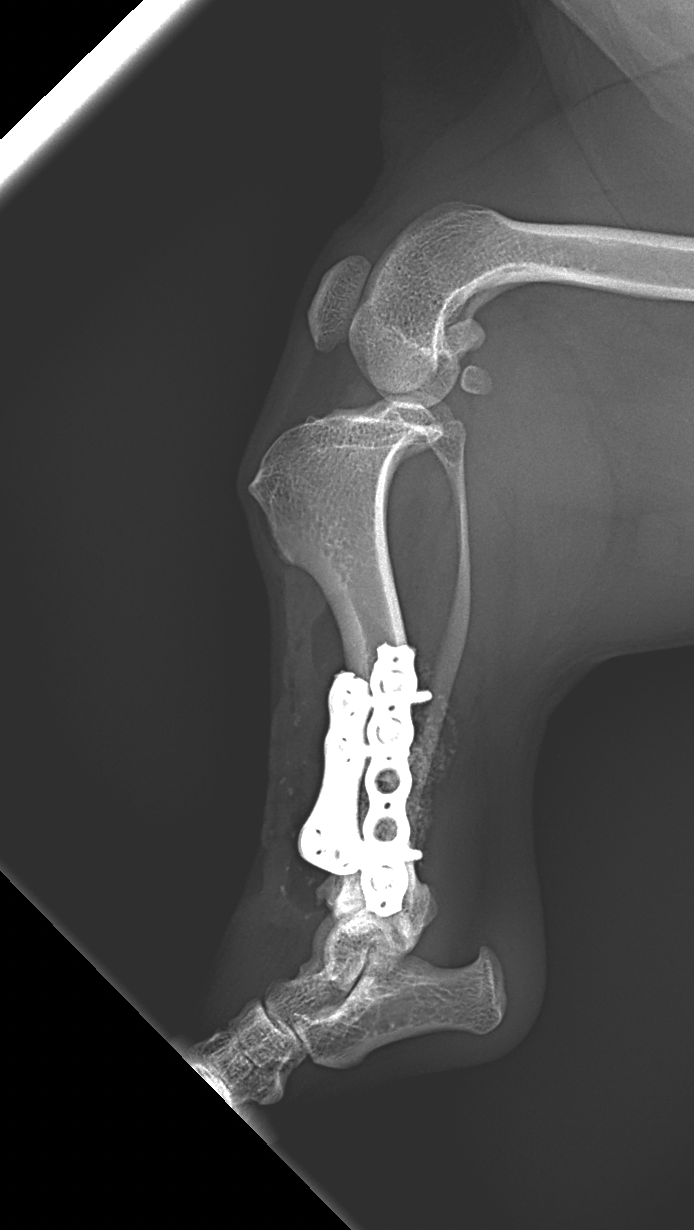

若齢ダックスの変形矯正手術:脛骨オープンウエッジオステオトミー

ダックスフントに特有の脛骨異形成症候群(Distal Tibial Deformity)に対して矯正骨切り術を実施しました。脛骨異形成症候群とは?短脚犬種に見られる骨の成長異常で、脛骨遠位が内側(内反/Pes Varus)に曲がり、歩行時の負担や膝蓋骨外方脱臼の原因にもなります。

開放型(オープンウエッジ)骨切り術を実施

変形の中心(CORA)を基準に適切な矯正角度を算出

プレートとスクリューでしっかり固定し、骨の癒合をサポート